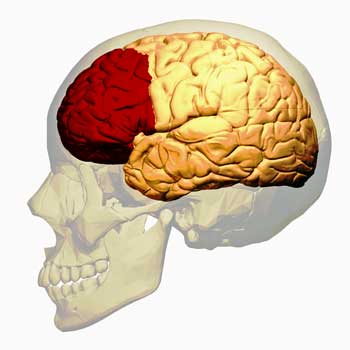

In the brain, the autonomic nervous system is also heavily intertwined with organs that regulate emotions. The fact that the brain organs most often implicated in ME/CFSFM are all associated with autonomic nervous system function, emotions and pain and sensory processing, suggests that all three are in play in these diseases.

- Insula – involved in emotions, motor control, cognitive functioning, pain processing, and the autonomic nervous system, movement.

- Amygdala – autonomic nervous system regulator, sensory stimuli processor, center of the fear response.

- Anterior cingulate cortex – autonomic nervous system regulator, stimuli and pain processing, emotional regulation.

- Prefrontal cortex – coordinates autonomic nervous system, neuroendocrine and behavioral responses to stress, seat of executive functioning.

The prefrontal cortex regulates sympathetic nervous system function, the cardiovascular system, sensory inputs, and the emotions. Could Garner have rehabilitated it?

The Japanese believe the prefrontal cortex (PFC) may be the key. The prefrontal cortex is an amazing, multidimensional brain organ. Not only does it regulate the PNS, but it’s also at the heart of “executive functioning” – which refers to reasoning, planning, judging, etc. It also regulates sensory inputs (physical sensations, over-stimulation), emotions (high emotional lability), attention span, working memory, planning, self-control and decision-making – none of which, at least in my experience, are doing particularly well. Plus, the PFC also appears, via the PNS, to regulate the cardiovascular changes occurring during movement.

The Japanese have found damage to the prefrontal cortex in ME/CFS. They believe that with the inhibitory brake of the prefrontal cortex gone, the sympathetic nervous system has been let loose, causing the brain to react to the slightest stimuli, leaving people with ME/CFS agitated, wired and tried, with distorted immune systems, etc.

It’s possible that the techniques Garner used helped him rehabilitate his prefrontal cortex. Studies show that meditation and mindfulness can increase prefrontal cortex activity and reduce the activity of other areas of the brain such as the anterior cingulate, which have been implicated in increased pain. The ability of mindfulness techniques to reduce pain is well known. Plus, garner’s decision to stop constantly assessing his symptoms could have taken some load off of his sympathetic nervous system.

Once Garner got his prefrontal cortex back in shape, his sympathetic nervous system may have calmed down, his immune functioning may have returned to balance, the blood flows to his muscles became more normal, etc.

A similar idea is that instead of properly filtering out sensory information, broken gates at the brainstem and spinal cord are allowing too much sensory information through, whacking the amygdala, insula, anterior cingulate cortex and other regions of the brain with tremendous streams of stimuli – and leaving them in a state of alarm.

In this scenario, finding ways to strengthen the prefrontal cortex allows it to calm down the fight/flight response, thus improving the immune response, possibly improving cardiovascular functioning, etc.